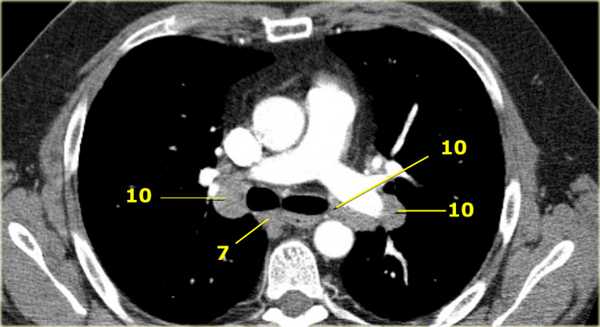

10. лимфатические узлы корня легкого

Лимфатические узлы корня расположены проксимальнее долевых узлов, но дистальнее медиастинальной дупликатуры и узлов промежуточного бронха справа.

Все лимфатические узлы 10-14 групп являются N1 узлами, так как они находятся вне средостения.